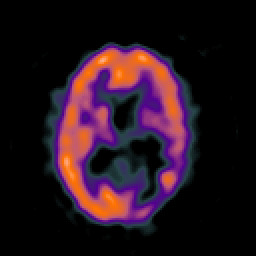

SPECT TC Study #8 -- Slice #31

[Home][Help][Clinical][Tour 1][Tour 2][Tour 3] Slice 31